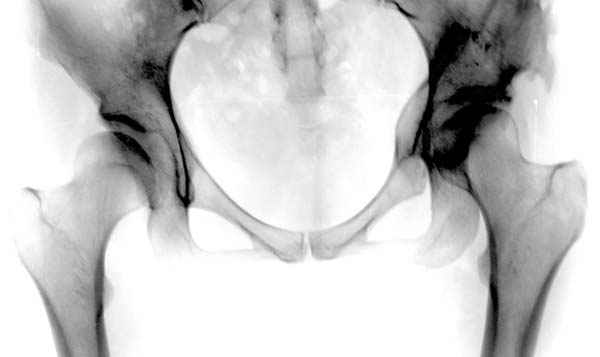

Рис.2 Та же трехмерная модель тазобедренного сустава без аналога связки головки бедра. Пружина динамометра удерживает тазовую часть модели от опрокидывания, поддерживая стабильность так же, как отводящие мышцы обеспечивают ее в отсутствии связки головки бедра.

Модель несовершенна, согласен, однако я экспериментировал и с импровизированной илеофеморальной связкой и ацетабулярной губой. Результат был тот же, подвижный узел замыкался посредством аналога СГБ. Для интереса я прилагаю фото., где сымитированы наружные связки и вертлужная губа, но без СГБ видно по показаниям динамометра, что данные структуры незначительно только на 0.5 кг разгружают аналог отводящих мышц. Почему модель получилась именно такой можно рассказать и подробнее если захотите…